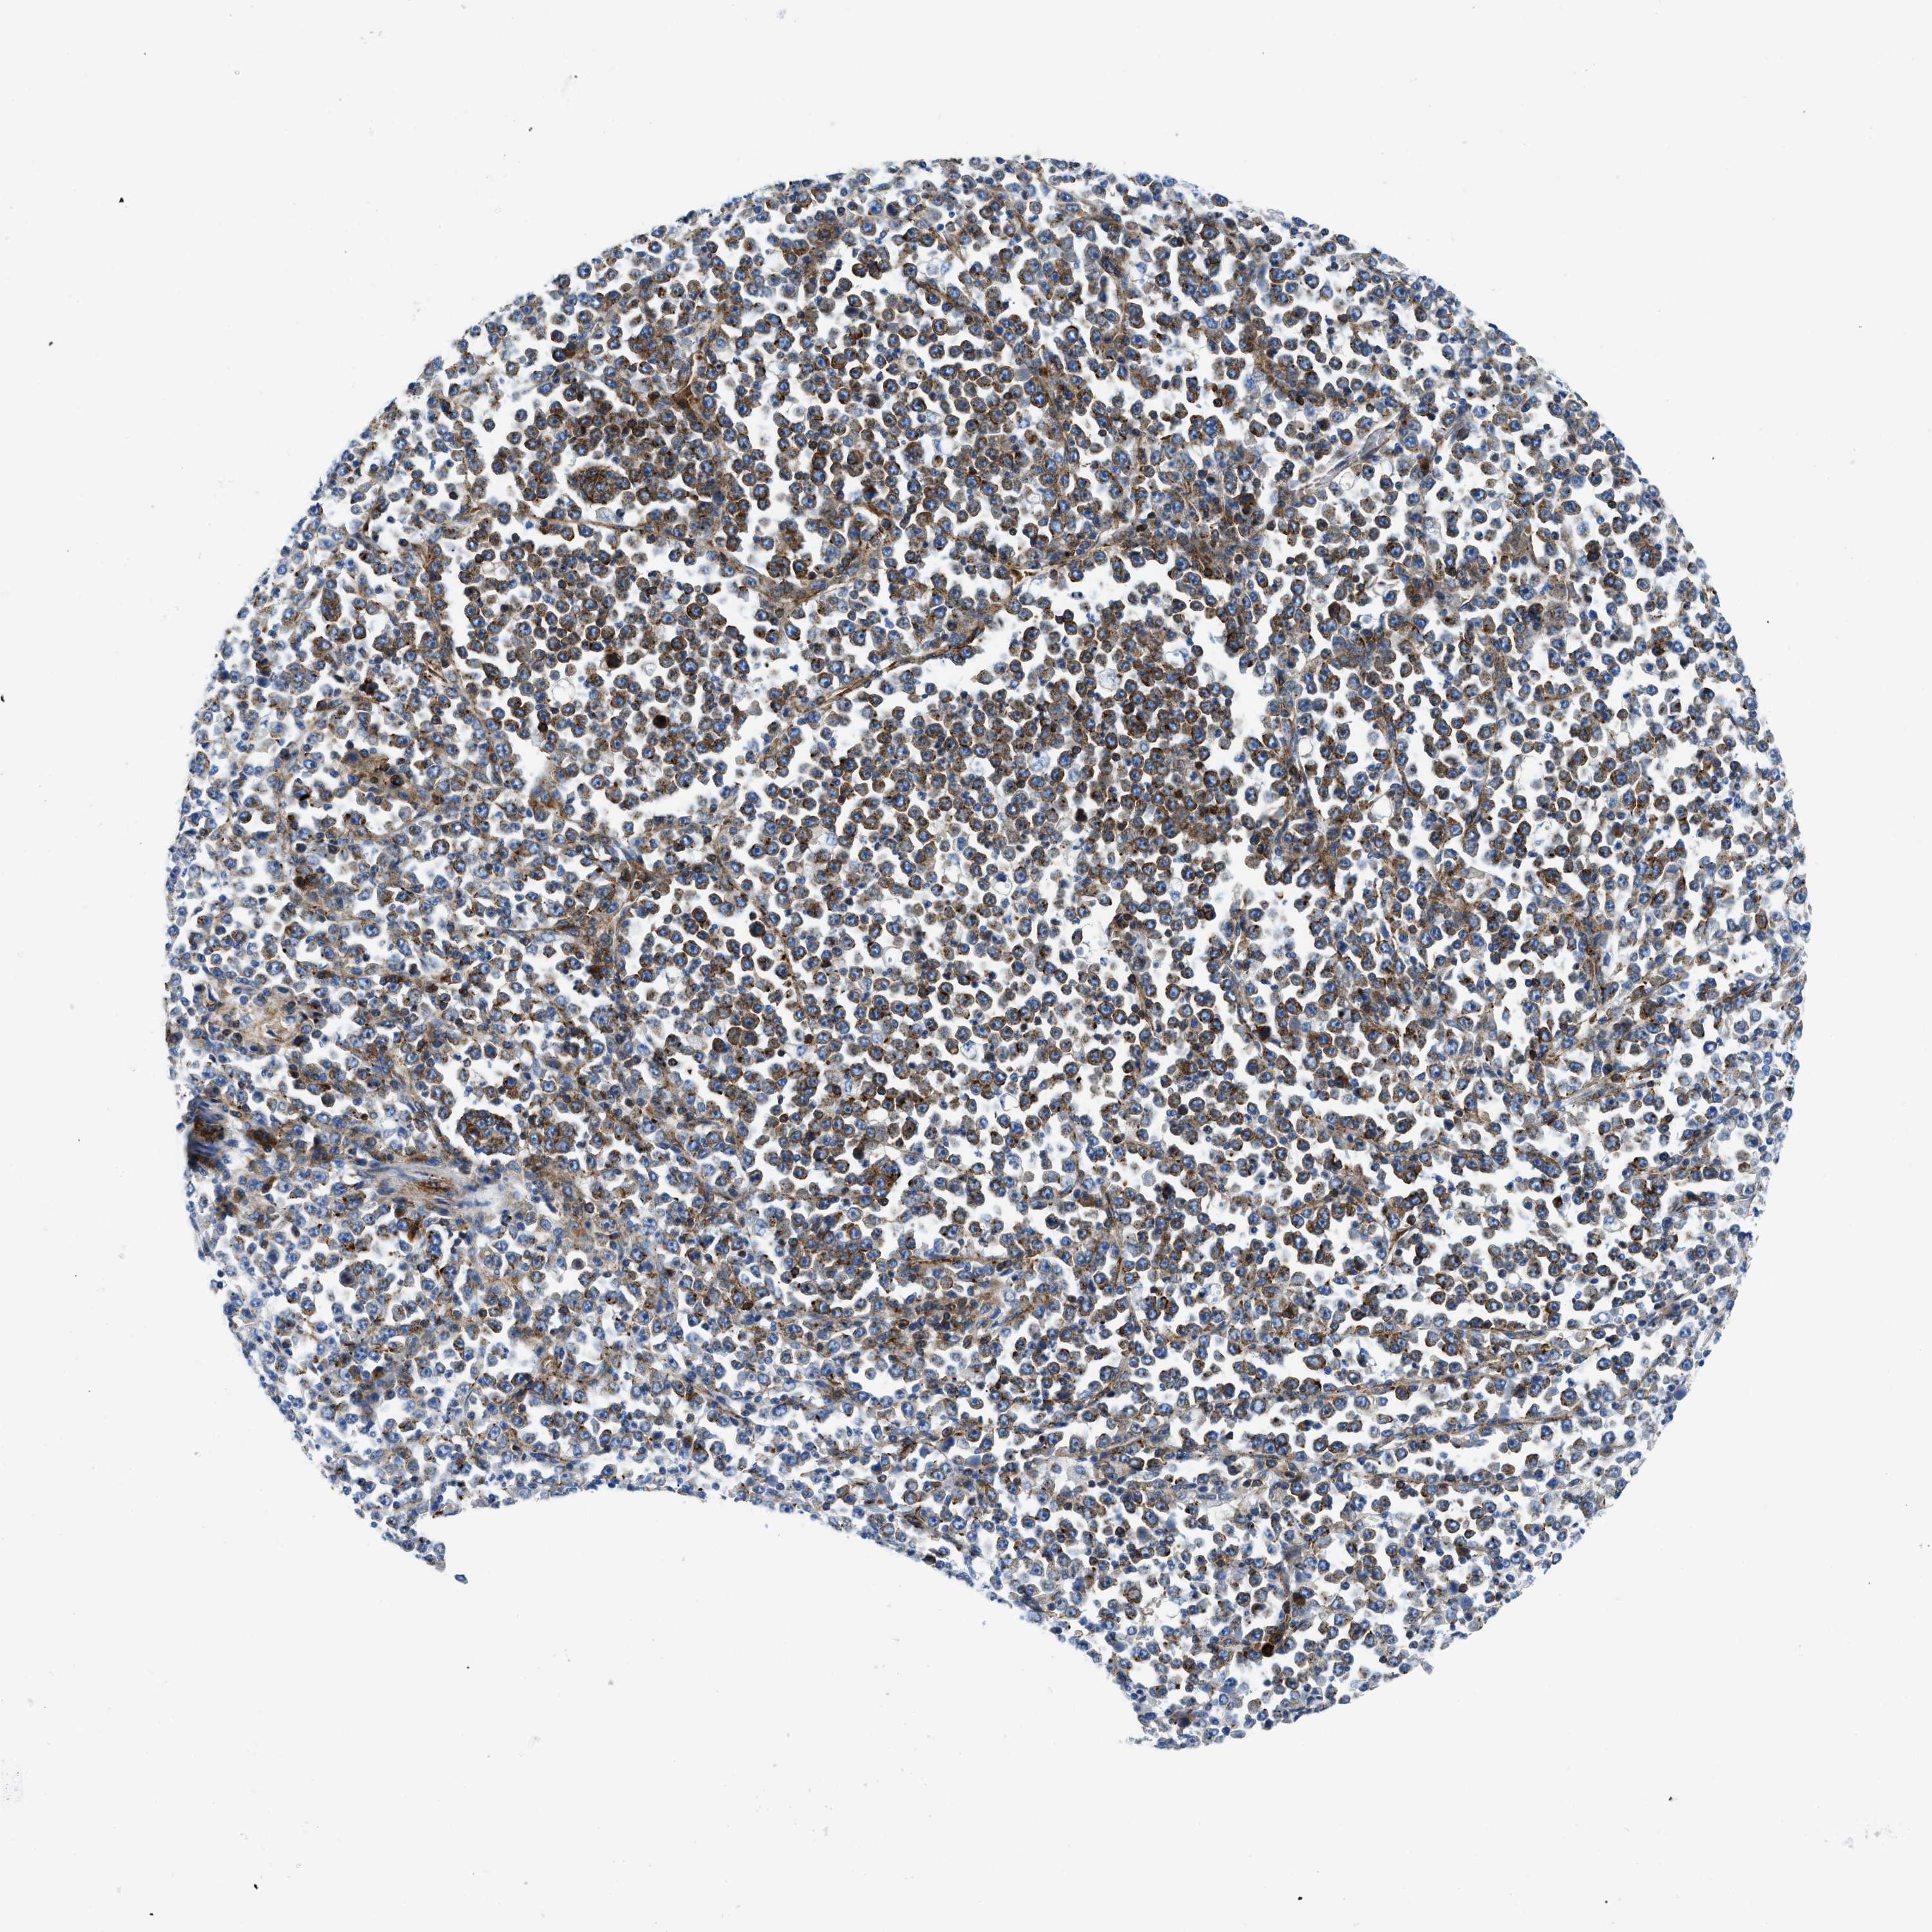

STOMACH CANCER - Protein expressioni

A mouse-over function shows sample information and annotation data. Click on an image to view it in a full screen mode. Samples can be filtered based on level of antibody staining by selecting one or several of the following categories: high, medium, low and not detected. The assay and annotation is described here.

Note that samples used for immunohistochemistry by the Human Protein Atlas do not correspond to samples in the TCGA dataset.

Antibody stainingi

Antibody staining in the annotated cell types in the current human tissue is reported as not detected, low, medium, or high, based on conventional immunohistochemistry profiling in selected tissues. This score is based on the combination of the staining intensity and fraction of stained cells.

Each image is clickable and will lead to virtual microscopy that enables deeper exploration of all samples and also displays staining intensity scores, fraction scores and subcellular localization as well as patient and tissue information for each sample.

Antibody HPA070199

Staining

High

Medium

Low

Not detected

Intensity

Strong

Moderate

Weak

Negative

Quantity

>75%

75%-25%

<25%

None

Location

Nuclear

Cytoplasmic/membranous

Cytoplasmic/membranous,nuclear

Adenocarcinoma, NOS